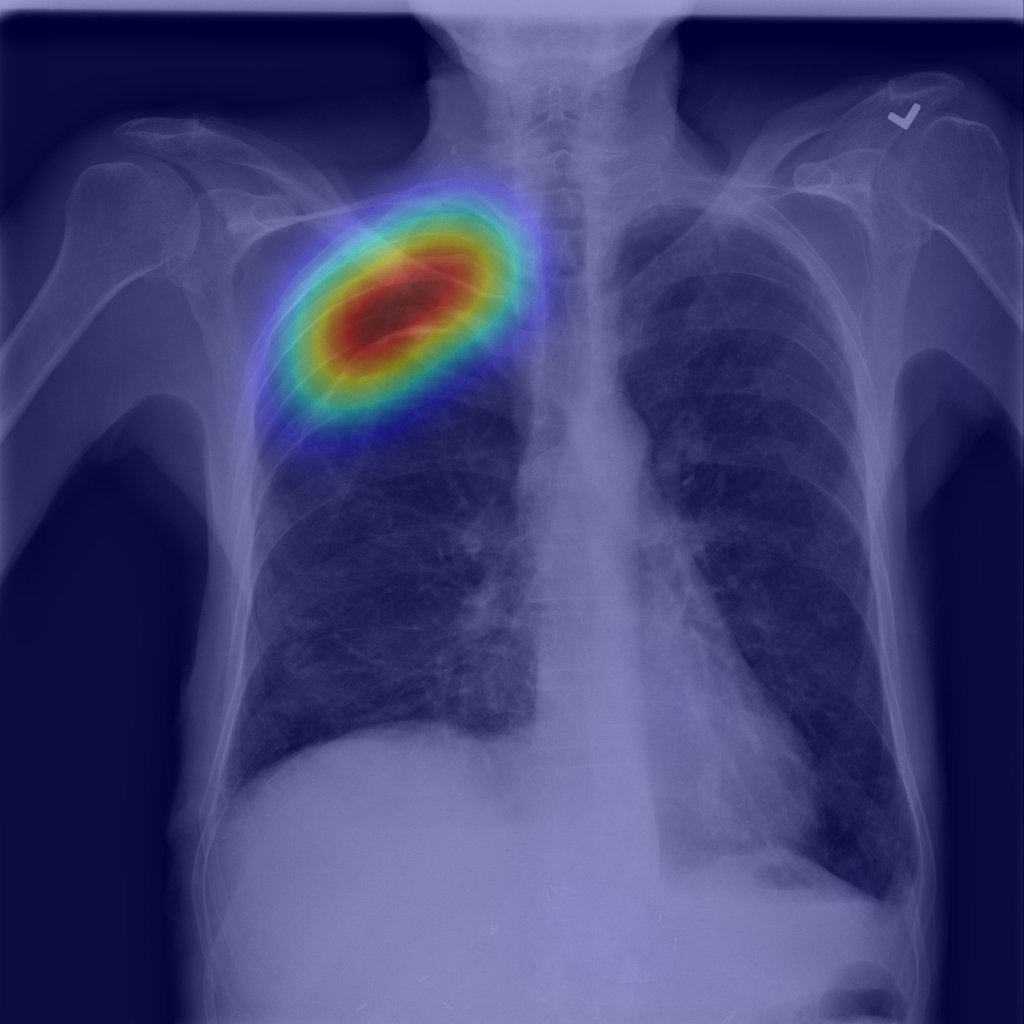

Refer to caption

(c) Step2.IRNet

Figure 1: Pneumothorax localization maps for (a) a random image from the test set at each consecutive step of our method: (b) map after CAM extraction, (c) improved map by IRNet trained on the outcomed of step 1, (d) prediction of U-Net trained on step 2 results, all compared to (e) ground truth mask.

We present method’s explainability via disease localization regions; cf. Figure 1. We provide qualitative results of segmentation on validation images from both datasets in Figure 2 and Figure 3. We show the resulting maps at each step of our method; the figures demonstrate how the performance improves after each step. We achieve comparable results to state-of-the-art method on PASCAL VOC 2012; cf. Table 4.